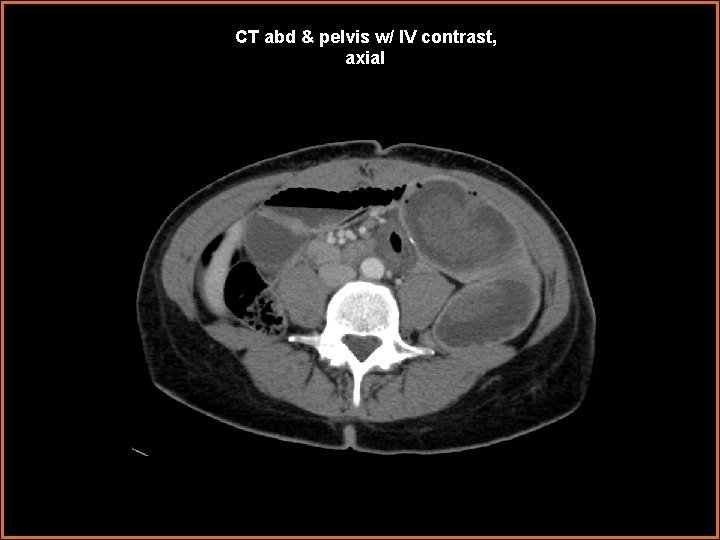

Case History 42 year-old female status-post gastric bypass operation within the last year presents with acute abdominal pain, nausea, and vomiting, for two days.

CT abd & pelvis w/ IV contrast, axial

Findings and Differentials Findings: -- several centimeters of small bowel lumen-within-lumen appearance—“target / bull’s eye” appearance, in axial cross-section -- mesenteric fat and vessels enter at the most proximal end of this small intestinal “telescoping” -- dilated immediate distal or outer aspect of the telescoping bowel-in-bowel segment -- however, decompressed distal small bowel and decompressing colon -- surgical anastomotic small intestinal clips in mid abdomen nearby segment of jejunum enters a segment of distal jejunum, near a post-operative site Differentials: • Intussusception • Midgut volvulus

Diagnosis Jejuno-jejunal intussusception, with partial small bowel obstruction converting to completion